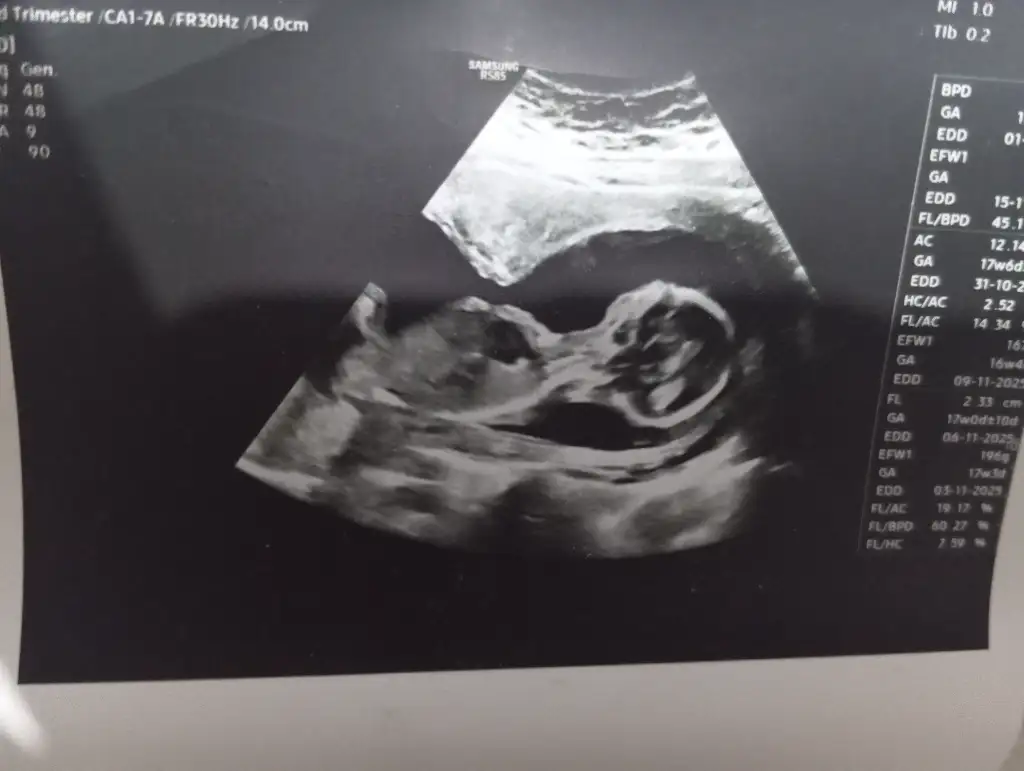

16 hafta daha nettir die düşünüyorumCinsiyetin önemi yok ama insan merak ediyor.Sizce bir dahakine de erkek deme şansı var mı

Ultrason foto varsa yuklermısınız son gittiğinizTeşekkürler canım:)

Ultrason foto varsa yuklermısınız son gittiğiniz

Cinsiyetiniz belli oldu muu, ben erkek gördüm sanki buradaSizce benimki ne anlıyor musunuz cinsiyetten çok merak ediyorum.

Belli oldu mu cinsiyetiniz acaba?İyi günler ben 24 haftalık biturlu gözükmüyor cinsiyeti bakabilirmisiniz